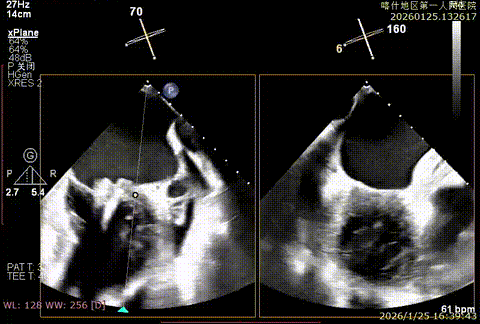

该例患者为VFMR,术前制定手术策略:患者二尖瓣重度反流,后叶严重栓系,心房心室扩大。患者瓣口面积4.5cm2,预计使用两枚XTR解决患者瓣叶脱垂和反流。考虑到先于2区进行钳夹,应该能获得足够的房间隔穿刺高度。术中经不断调整穿刺位点,最终穿刺高度4.4cm。成功穿刺后将第一枚XTR送入二尖瓣正上方,进行弹道测试Orientation调整后,最终定位于2区正上方下左心室。第一枚夹子在左室成功捕捞和钳夹瓣叶后,瓣叶反流程度显著降低,夹子外侧仍见部分反流,随后在第一枚夹子外侧再次放置一枚XTR,瓣叶反流程度进一步降低至微量。通过TEE观察,二尖瓣双孔组织桥稳定,跨瓣压差3mmHg,肺静脉逆流改善明显,手术安全结束。

X-plan重度反流

3D enface后叶栓系

3D enface观察反流